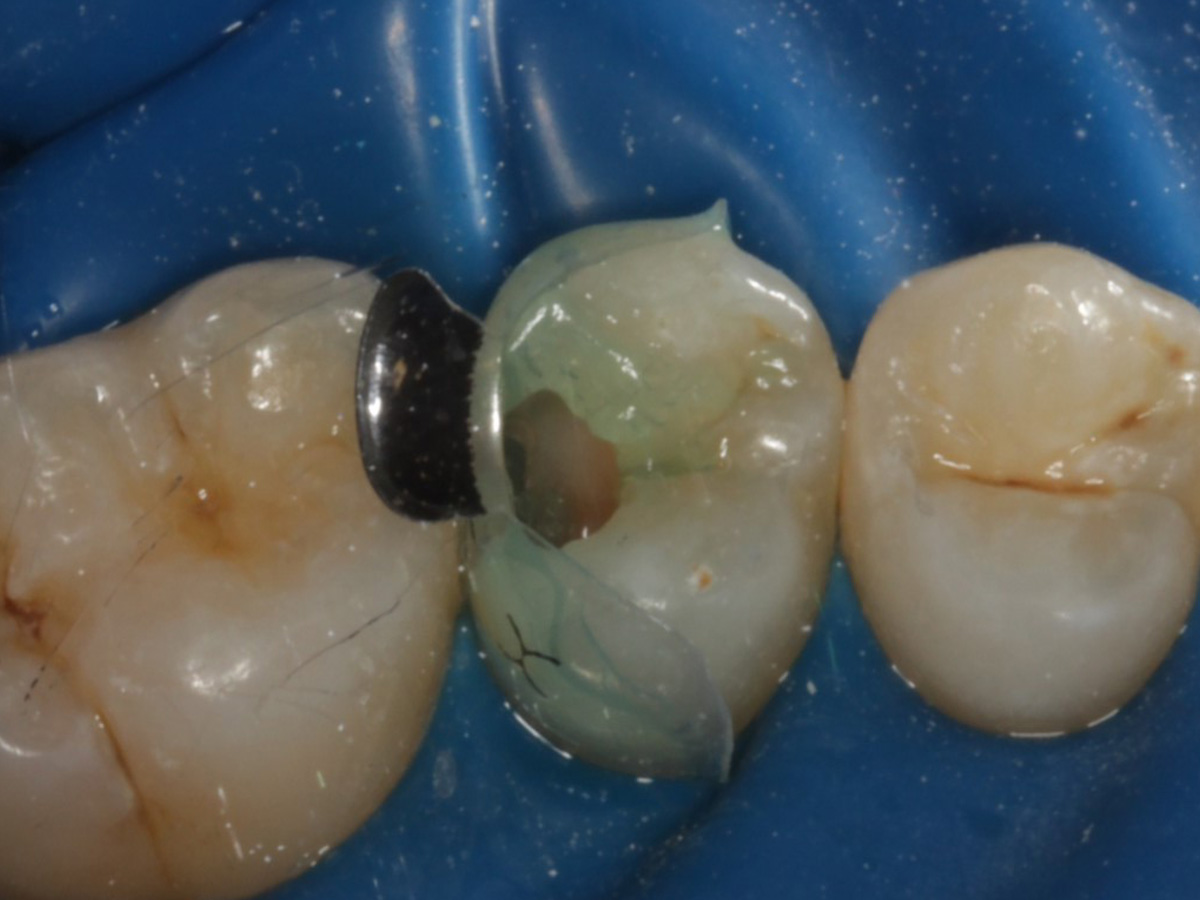

Abbildung 1

Approximalraumkaries an Zahn 25 distal

Schutz des Nachbarzahnes und des Kofferdams mit wiederverwandter Bioclear Biofit Matrize (gereinigt und sterilisiert); Separation zur Applikation der Matrize mit Heidemannspatel